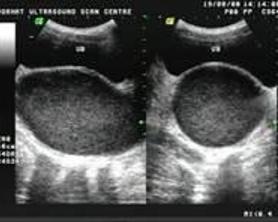

۞ 处女膜闭锁的检查